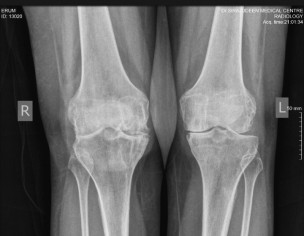

Not sure which treatment you are referring to. the Xrays show quite a bit of damage for someone who is just 40 yrs old. I suspect the patient may have inflammatory arthritis causing this. for this she should consult a qualified Rheumatologist for specialist treatment

I agree with Dr. Ashar, you are too young to have these x rays. See a rheumatologist soon.